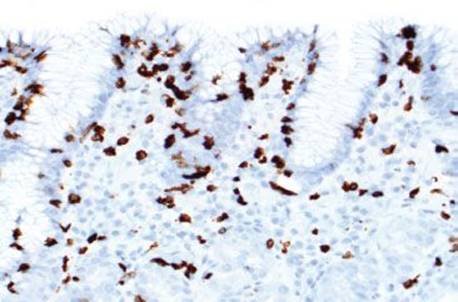

Figure 2.123 Lymphocytic gastritis pattern (CD3 immunostain). The corresponding CD3 immunostain from the previous case (Fig. 2.122) confirms that the intraepithelial lymphocytes are predominantly CD3+ T-cells. Immunophenotyping the IELs is not required for diagnosis.

Figure 2.124 Lymphocytic gastritis pattern (CD4 immunostain). The corresponding CD4 immunostain highlights a small population of CD4+ T-cells.

Figure 2.125 Lymphocytic gastritis pattern (CD8 immunostain). The corresponding CD8 immunostain highlights shows that the majority of the IELS are CD8+ T-cells.

Lymphocytic gastritis differs from chronic gastritis by the presence of increased intraepithelial lymphocytes (IELs), defined as more than 25 intraepithelial lymphocytes per 100 epithelial cells (Figs. 2.120–2.126).38,91–97 The term “lymphocytic gastritis” was originally used to describe the histologic counterpart to “varioliform” gastritis (i.e., thickened rugal folds and erosions), but subsequent studies have shown this association in only 3.9% to 30% of cases. More commonly, the endoscopic image shows erythema but up to 50% of patients have a normal endoscopic appearance. Although the etiology of the inflammation remains unknown in up to 20% of cases, common associations include infection (e.g., Helicobacter, HIV), celiac disease and other immune-mediated disorders (common variable immunodeficiency, Crohn disease, lymphocytic enterocolitis), medications, and neoplasia (Figs. 2.127–2.142).98 As a result, recognition of the lymphocytic gastritis pattern can serve as an important red flag to the underlying diagnosis and, consequently, lead to effective therapy with resolution of symptoms. The changes affect the entire stomach, but intraepithelial lymphocytes are most evident in the oxyntic mucosa, and are more prominent in the superficial epithelium than the glands. Most cases show expansion of the lamina propria with a mixed lymphoplasmacytic inflammatory infiltrate, in addition to the intraepithelial lymphocytosis (Fig. 2.121). Regenerative and hyperplastic changes in the surface epithelium may be present, analogous to the surface changes seen with intraepithelial lymphocytosis of the small and large bowel. Immunolabeling identifies these as CD3+ T cells, with about 80% showing a cytotoxic/suppressor CD8+ phenotype. Most patients respond to treatment of their associated condition, when a known etiology is present (i.e., successful eradication of Helicobacter usually leads to reduced symptoms and decreased inflammation in biopsies, and adherence to a gluten-free diet typically results in clinical and histologic improvement in patients with celiac disease). Others advocate empiric Helicobacter eradiation, even in Helicobacter-negative patients. In general, immunosuppressive medications are reserved for those who fail gluten withdrawal and whose intraepithelial lymphocytosis involves the stomach, small, and large bowel. Untreated lymphocytic gastritis may persist for years, although spontaneous remission has been reported.